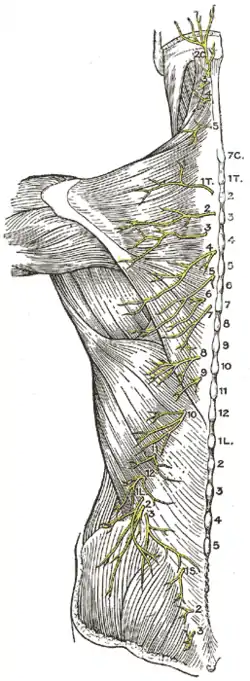

The posterior divisions of the sacral nerves.

The posterior divisions of the sacral nerves.